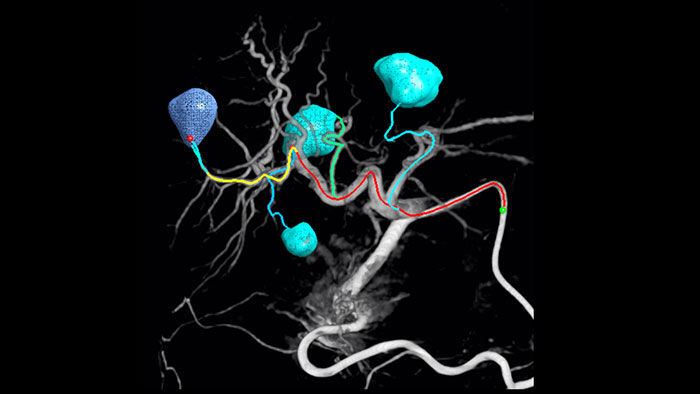

A adoção de técnicas de quimioterapia/radioembolização como TACE e SIRT impulsionam a necessidade de padronização e eficiência. Caso após caso, você precisa localizar os tumores, identificar todos os vasos alimentadores e planejar/executar a abordagem intervencionista apropriada de forma confiável e consistente. Nossa solução de Detecção Automática de Alimentação pode aprimorar de forma significativa a detecção da artéria alimentadora em comparação com o uso isolado da Tomografia Computadorizada de Feixe Cônico. O recurso EmboGuide facilita a maximização da eficácia de seus procedimentos de TACE devido ao seu potencial de aumento da sensibilidade, redução de falsos positivos e maximização do acordo interleitores.1

A capacidade de detectar e diferenciar nódulos hepáticos e identificar vasos alimentadores muito pequenos é fundamental para determinar a terapia adequada. Navegar para a região de interesse alcançando todos os alimentadores e, ao mesmo tempo, manter-se seletivo quanto à lesão aumenta as chances de sucesso. A confirmação do desfecho do tratamento e do sucesso do tratamento enquanto o paciente ainda está na mesa aumenta a confiança no desfecho clínico.